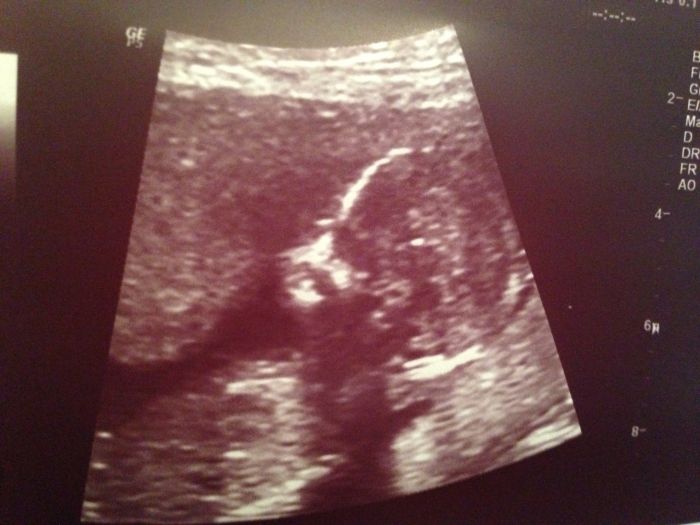

Autor: BaruSka 31.7.2014 v 12:20

[605239] ahojda nadherna fotecka :-) hlavne ze je vse v poradku ;-)

Autor: Brozanka 31.7.2014 v 12:24

[605239]Moni,krásná fotečka..hlavně,že je mimčo v pořádku a plodovka se ti vyhla obloukem stejně jako mě. A bříško nám sem přidáš?

Zdravím nově příchozí maminu BaruSku. Máš krásný fotky. A koukám, že holčičí jméno máš vybrané jako já